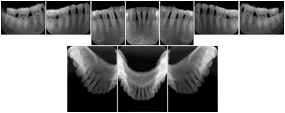

2. A patient requests cosmetic surgery to enhance their facial appearance. The case requires consultation between an orthodontist in New York and an oral surgeon in California. The cephalometric series of 2D projections constructed from a volumetric CT data set that is used for the discussion is arranged by a Structured Display for transfer between the two practitioners.

Cephalometric Series Structured Display

Figure OO-2. Cephalometric Series Structured Display

3. A dental provider wishes to capture a series of DICOM IO images for the patient’s dentition. The tooth morphology, teeth are divided into molars, premolars, canines and incisors, and a number of images for each jaw. The anatomic information was captured utilizing the triplet of schema. This standard code sequence is based on ISO 3950-2010, Dentistry - Designation system for teeth and areas of the oral cavity.

Every IO image should have anatomic information either through the primary or modifier sequence.

In most standard cases, images are oriented in structured layouts. These structured displays are useful to be shared between providers for reference purposes.

Table OO.1.1-1 shows structured display standard templates, where Viewset ID is based on the Japanese Society for Oral and Maxillofacial Radiology (JSOMR) classification provided by JIRA (Japan Medical Imaging and Radiological Systems Industries Association, www.jira-net.or.jp). Expected or typical teeth to be imaged location, region and designation codes are based on ISO 3950-2010, Dentistry - Designation system for teeth and areas of the oral cavity. For all the hanging protocols listed in OO.1.1-1, the value to use for Hanging Protocol Creator (0072,0008) is "JSOMR" and the value to use for Hanging Protocol Name (0072,0002) does not include "JSOMR" (e.g., "DL-S001A", not "JSOMR DL-S001A").